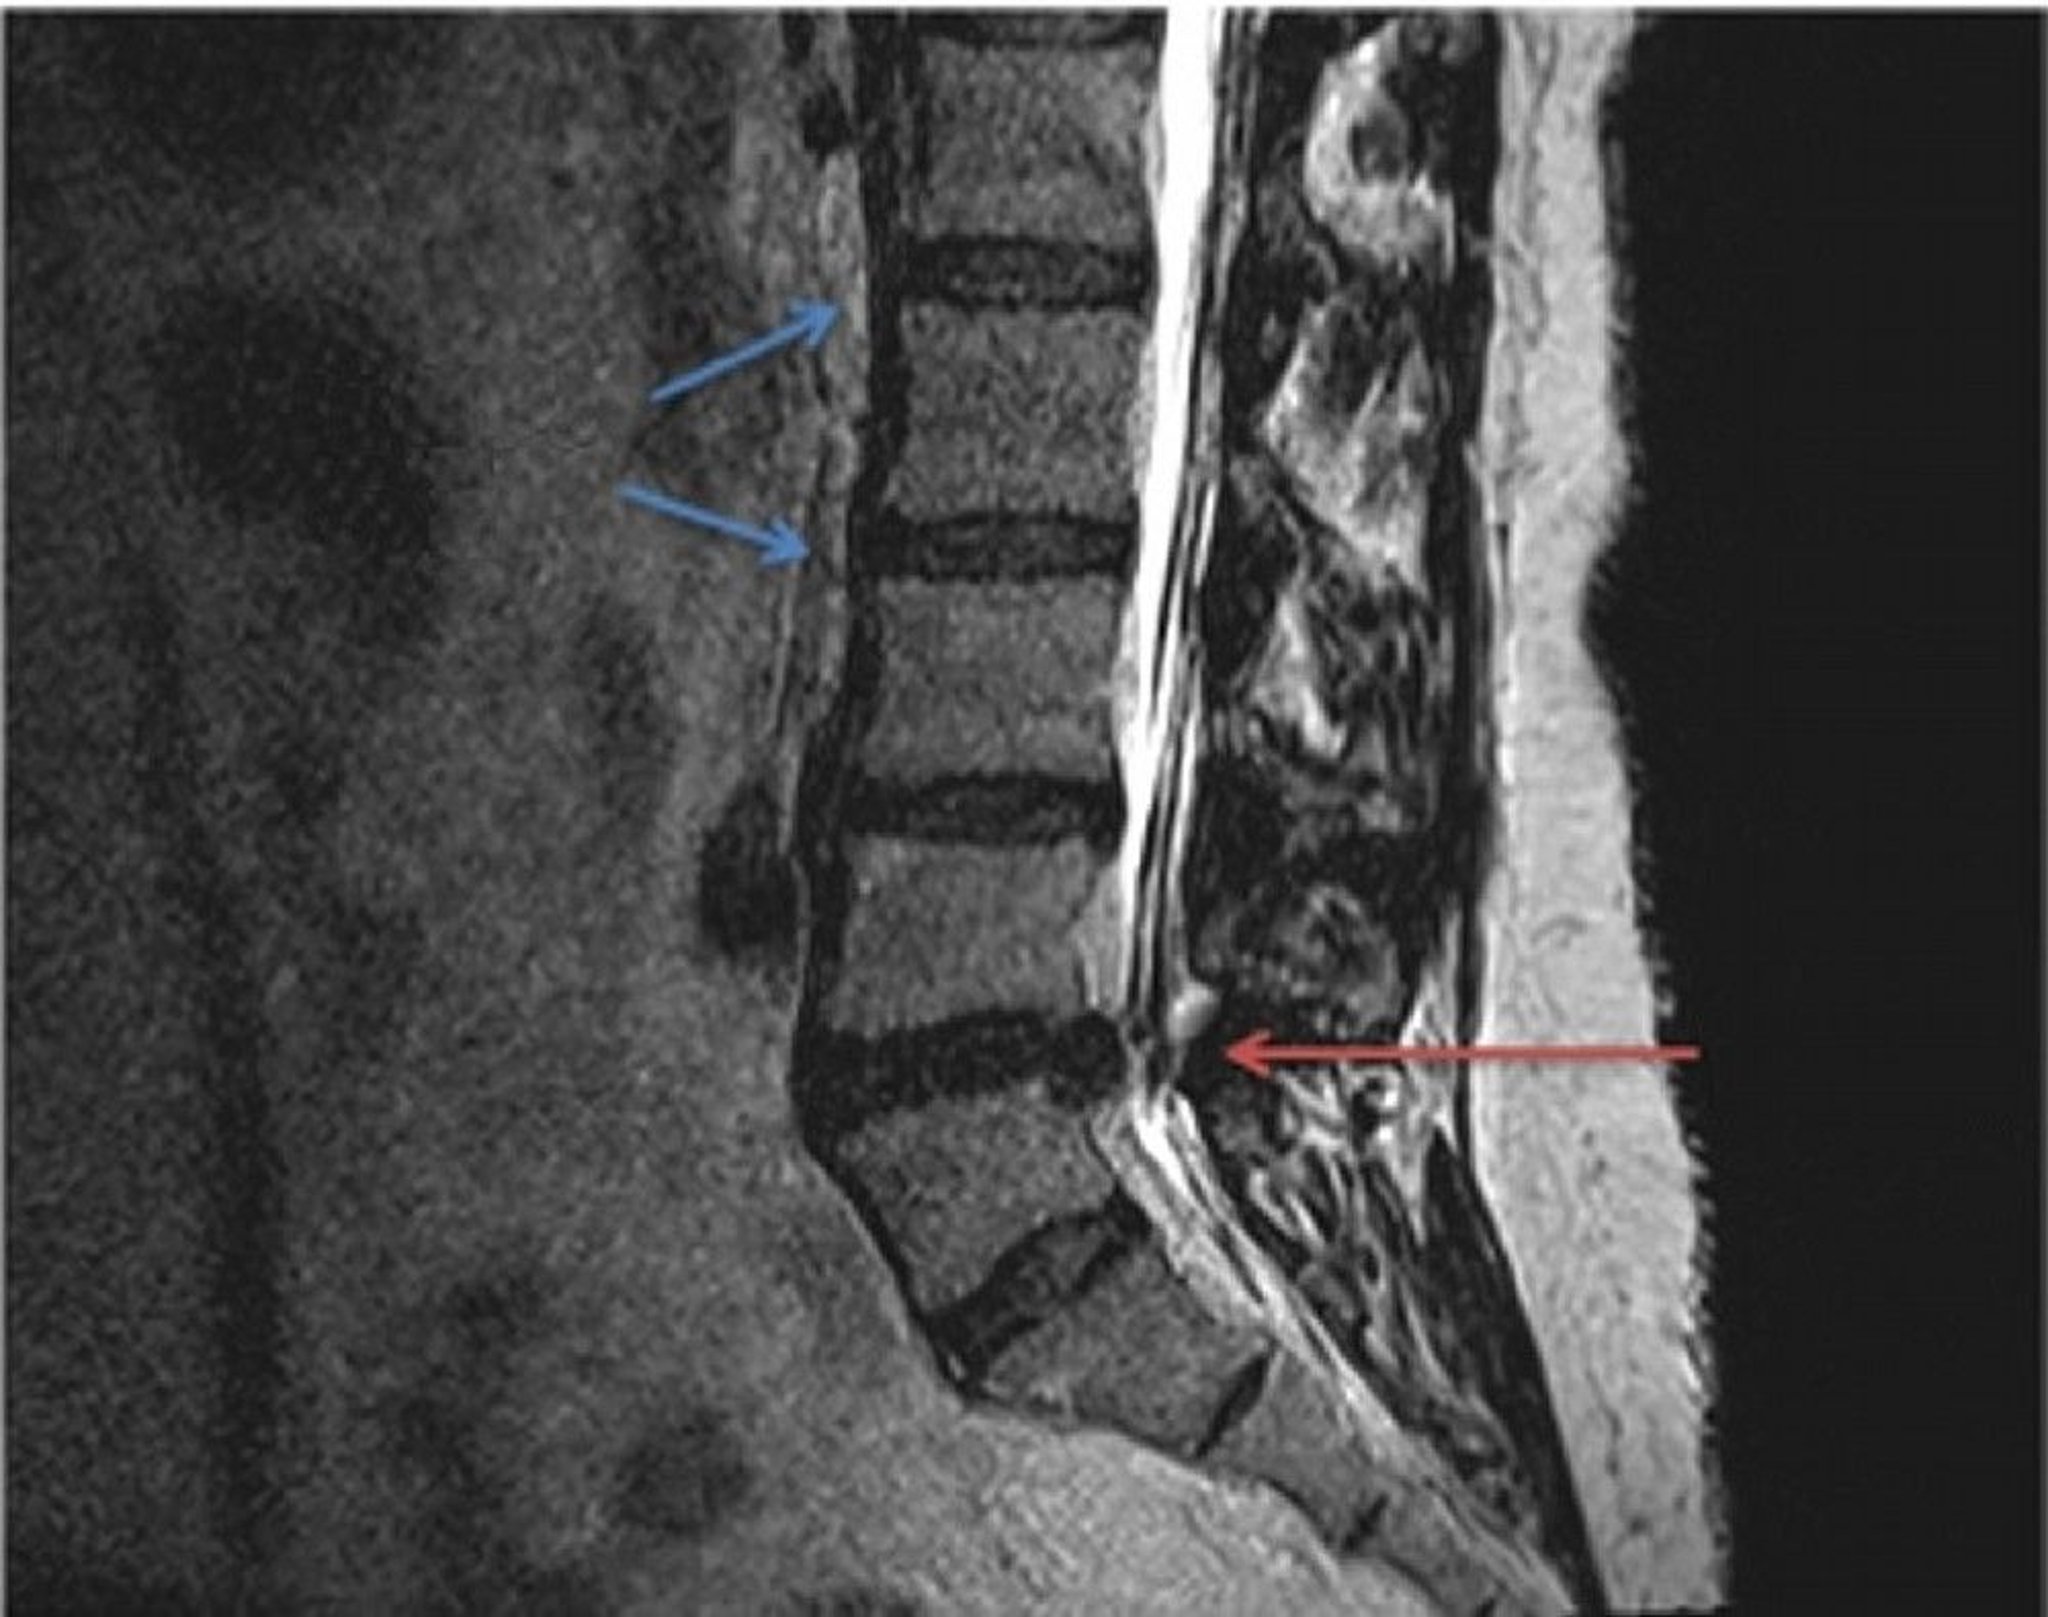

MRIのT2強調像における,正常(青矢印)と腰椎椎間板ヘルニアの解剖の比較。脊椎L4とL5の間に生じた椎間板ヘルニア(赤矢印)が,脊髄からのびる脊髄神経を絞扼し,局所的または放散する圧迫と疼痛を引き起こしている。